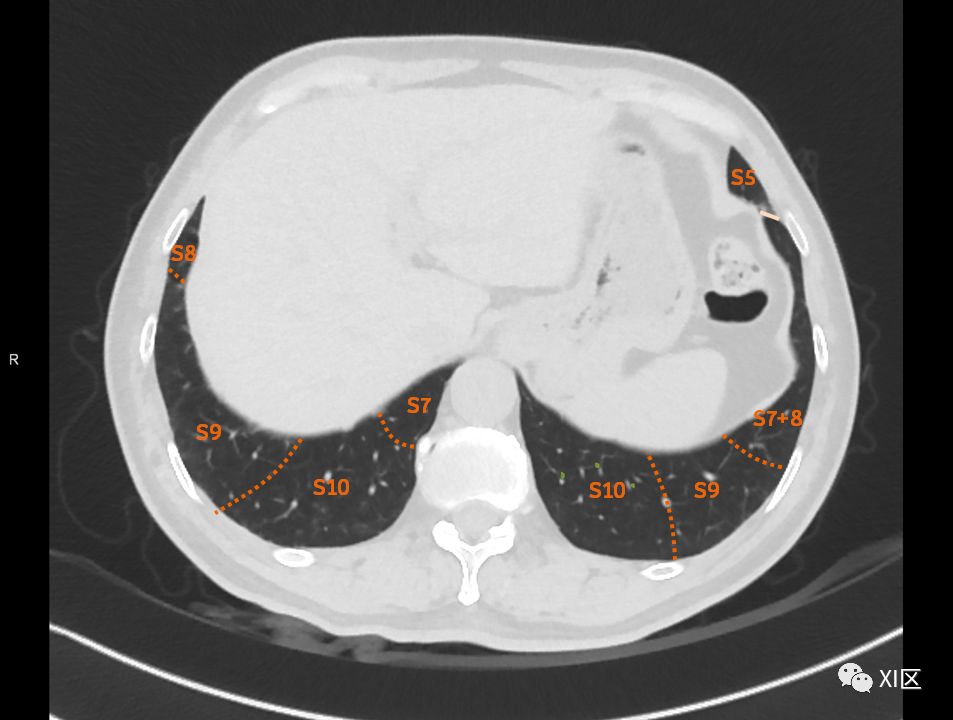

在进行肺的分段时,可以上下观察浏览,沿着相应气管的走形可以更容易准确地进行分段。

肺的断层分段示意图